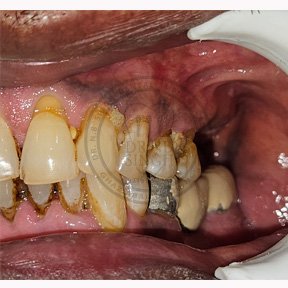

Case – 11 Baleram